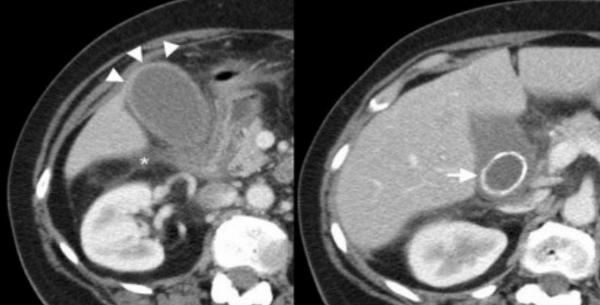

Ксантогранулематозный холецистит.

Ксантогранулематозный холецистит — это воспалительное заболевание, характеризующаяся тем, что в стенке желчного пузыря образуются ксантомы и гранулемы. При исследовании выявляют утолщение стенки желчного пузыря, уменьшение органа в размере, а также интрамуральные узелки, которые визуализируются, как гипоэхогенные включения на УЗИ и гиподенсные на компьютерной томограмме. Данные включения схожи с включениями при карциноме желчного пузыря.

УЗИ и КТ желчного пузыря. Ксантогранулематозный холецистит. Слева на УЗИ визуализируется (помечено стрелками) утолщение стенки желчного пузыря с интрамуральным включением и с камнем в просвете органа. Справа на КТ выявляется утолщение стенки с гиподенсными включениями.

Выше представлено КТ пациента 71 года с ксантогранулематозным холециститом. Постконтрастное КТ. Визуализируется утолщение стенки желчного пузыря с включениями, которые соответствуют абсцессу или фокусам воспаления.

КТ желчного пузыря/Рак желчного пузыря

Наиболее часто встречаемый рак желчного пузыря является карцинома. Карцинома желчного пузыря занимает пятое место по частоте встречаемости среди раков желудочно-кишечного тракта. Чаще его обнаруживают случайно (в 2% случаях) при гистологической проверке после холецистэктомии. Карцинома желчного пузыря выявляется на последних стадиях заболевания так, как себя не проявляет клинически на ранних. Специфических признаков при карциноме желчного пузыря также нет. Рак может поражать желчный пузырь диффузно, целиком стенку или пристеночно. Карцинома желчного пузыря имеет схожую картину с ксантогрануломатозным холециститом, но при постановке диагноза радиологу помогают такие находки:

УЗИ (слева) и КТ (справа) желчного пузыря. На УЗИ ярко выраженное утолщение стенки желчного пузыря (указаны белыми стрелками). Множественные камни в просвете желчного пузыря (указано стрелкой). Компьютерная томография с контрастным усилением. На КТ визуализируются утолщение стенки с внутристеночными гиподенсными включениями. На КТ также выявлено, что процесс распространился на печень (указано стрелкой).